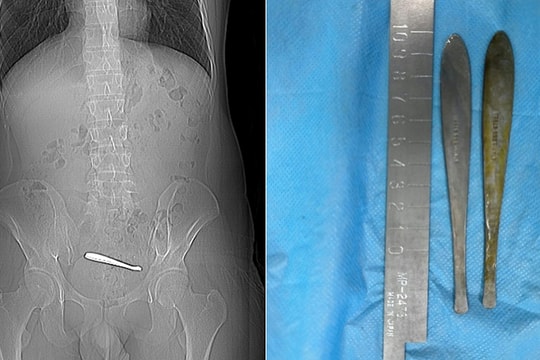

Nuốt kim khâu khi chơi, bé 11 tuổi suýt thủng ruột

27/11/2025 14:18

Bé 11 tuổi từ Lâm Đồng được chuyển đến TP HCM khi gia đình phát hiện em đau vùng cổ và hình ảnh X-quang cho thấy dị vật nghi kim khâu trong đường tiêu hóa.